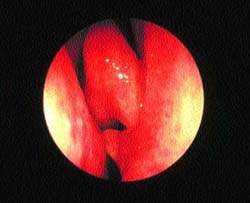

| Рисунок 6. “Шпора” перегородки носа, врезающаяся в среднюю носовую раковину, — возможная причина “контактных болей” |

Недавно возник интерес к так называемой контактной боли. Предполагается, что при этом состоянии носовая перегородка находится в патологическом контакте с боковой стенкой носа. Обычно это происходит, когда от перегородки отходит острая шпора, упирающаяся в среднюю носовую раковину (рис. 6). Как правило, пациенты жалуются на боль вокруг центральной части лица, отдающую в лоб и глазницы.